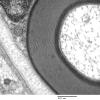

PERIPHERAL NEUROPATHY

3 NORMAL MYELIN & SCHWANN CELLS

1 Myelin